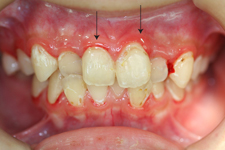

2. 歯肉炎

炎症が歯ぐきのみに見られます。歯ぐきの縁が赤く腫れ、歯磨きの際に出血することがあります。この状態を放置すると、歯周炎へと進み最終的には歯が抜け落ちてしまいます。

3. 軽度歯周炎

歯周ポケットが3mm以内で、歯の揺れる幅が0.7~1.0mm以内の状態を軽度歯周炎と呼びます。骨が少し溶け始めますが痛みを伴わないので気付きづらい状態です。

歯磨き指導(Teeth Brushing Instruction)を行い、ご自身で丁寧に歯磨きをしていただくこと、また、クリニックにて歯石の除去も合せて行います。

▼歯磨き指導だけで改善した例です。

治療前

治療後

▼保険治療の範囲で超音波スケーリングを行い、歯肉の腫れが和らぎました。